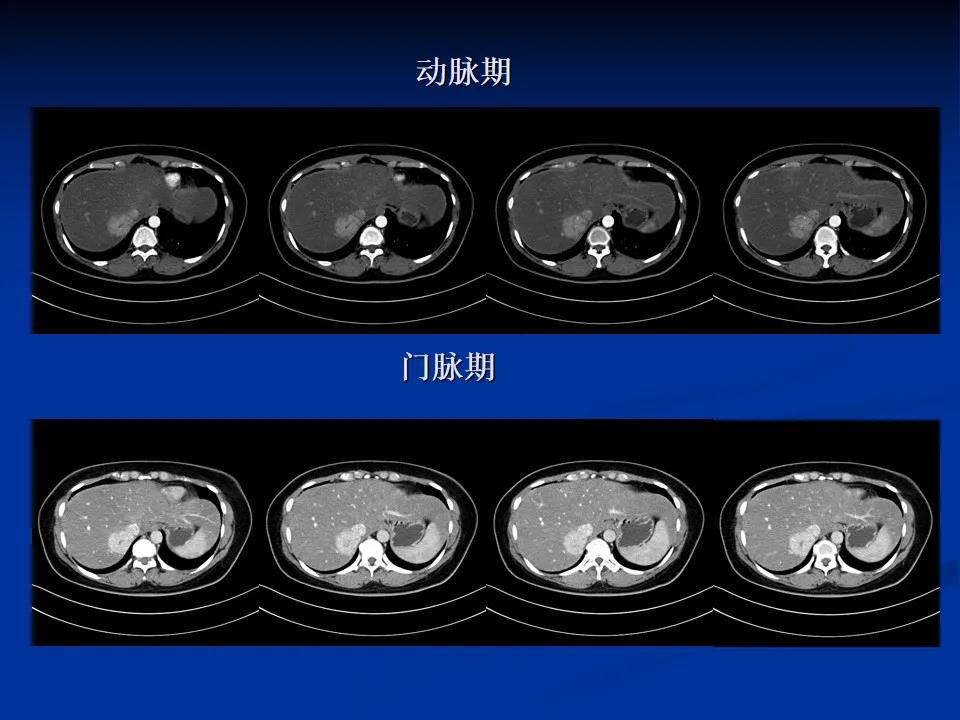

CT动态增强扫描+MRI平扫

诊断意见为肝右叶后上段富血供肿块,倾向于良性,以FNH(肝局灶性结节增生)或肝腺瘤相鉴别,以前者可能大。为进一步明确肿瘤性质及明确下一步诊疗方案,行肝特异性对比剂增强扫描。